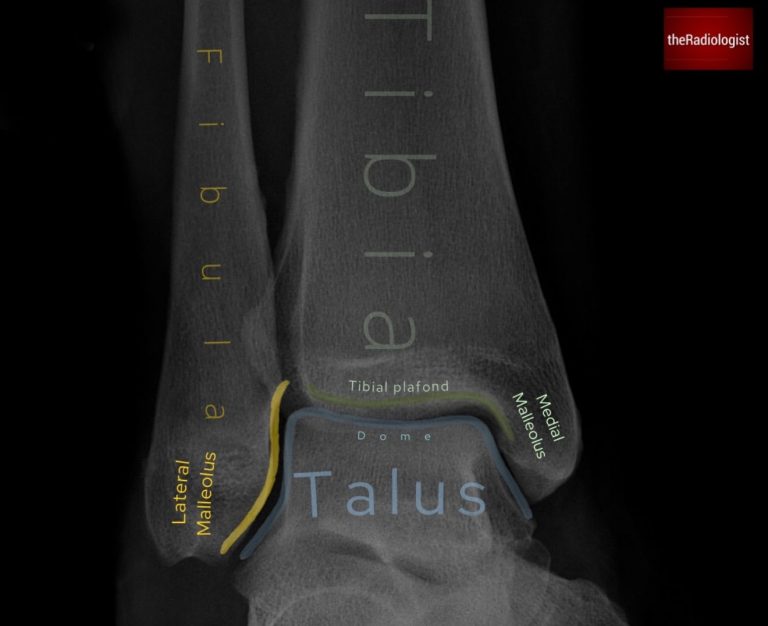

3. Ankle mortise

Now trace the mortise joint: the tibial plafond with the medial and lateral malleoli and the talar dome. The joint space should be symmetric and uniform. Any asymmetry could represent a ligament injury with or without a fracture.

The mortise view lets you assess the mortise joint accurately – make sure the joint space is symmetric and uniform.

4. Medial clear space

Measure the distance between the medial malleolus and the talus. It should be <4 mm and roughly equal to the superior joint space. In the context of a distal fibula fracture, widening could mean deltoid ligament disruption and lateral talar shift, which makes the injury unstable.

Meaure the medial clear space: this should be less than 4 mm and roughly equal to the superior joint space.

5. Lateral clear space

Measure the lateral clear space 1 cm above the tibial plafond. Normal is <6 mm. Anything wider suggests a syndesmotic injury ie. damage to the distal tibiofibular ligaments. This usually means surgical fixation is needed.

Meaure the lateral clear space: measure 1 cm above he tibial plafond. This should be less than 6 mm.